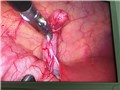

Khoa Ngoại TH- Trung tâm y tế Nghi Xuân vừa phẫu thuật nội soi thành công viêm ruột thừa ở vị trí hiếm gặp ở dưới gan cho bệnh nhân nhi 6 tuổi.